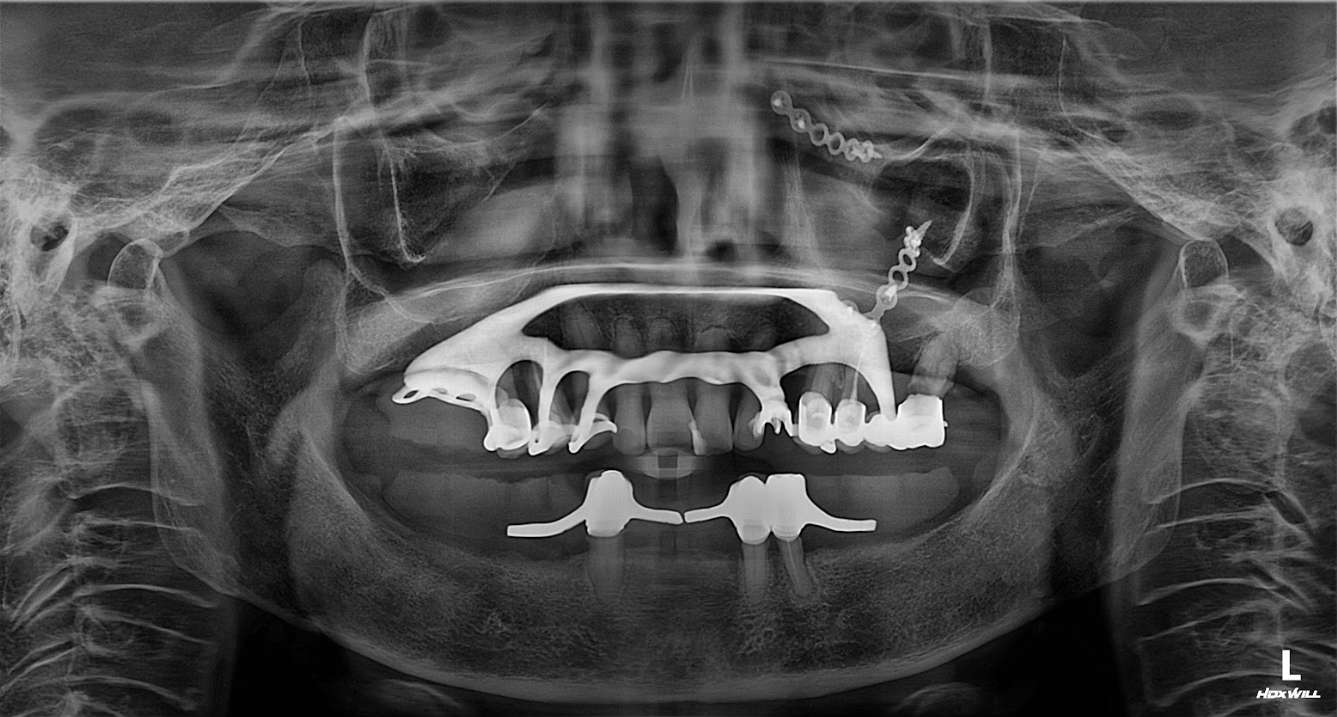

1. Thăm khám & đánh giá tình trạng xương hàm

Chụp CT ConeBeam 3D để phân tích mật độ xương.

-

Đánh giá mức độ tiêu xương nặng, khả năng đặt Implant.

Xác định giải pháp: Trồng Implant toàn hàm bằng công nghệ Digital Implant.